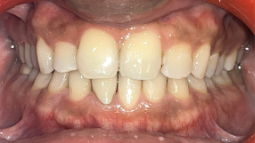

A comprehensive oral examination shows an Angles Class 1 molar relation with unilateral anterior cross bite. There was asymmetric overjet and overbite with anterior crowding in upper and lower arches.

The orthodontic treatment successfully corrected the patient’s anterior crossbite, aligning both upper and lower arches. This intervention resulted in a symmetric overjet and overbite, enhancing his smile aesthetics and overall oral function.

This orthodontic treatment addressed issues concerning the patient using a non extraction approach. Illusion Aligners were delivered to achieve the treatment objectives as it provides aesthetic look and superior quality. The results included successful crossbite correction and alignment of both the arches. The establishment of symmetric overjet and overbite was achieved as well.